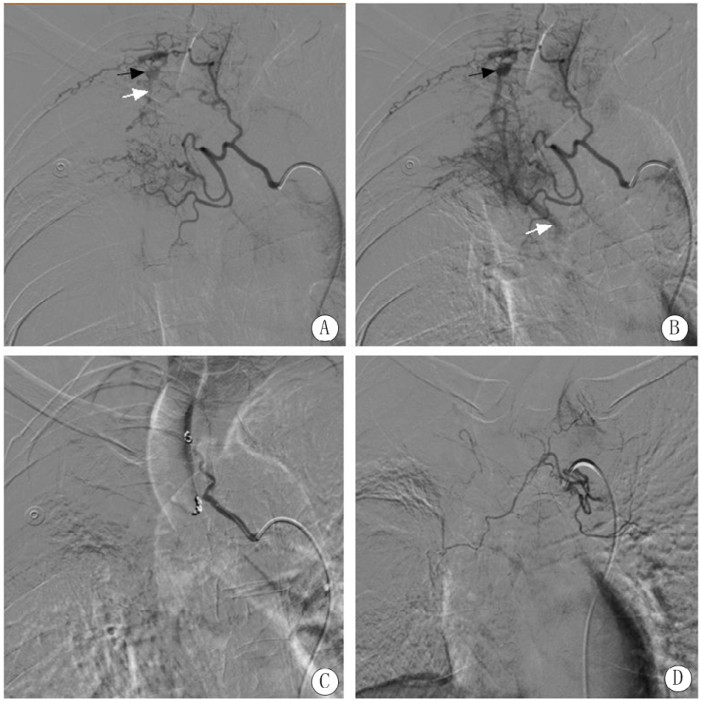

入院后每日咯血约500 mL,患者家属要求行介入栓塞止血,术中患者不间断咯血,数字减影血管造影(digital substraction antiography, DSA)示右第四肋间动脉增粗,远端可见肺静脉分支显影,右支气管动脉主干增粗与右第3肋间动脉共干,支气管动脉远端分支增多杂乱,肺组织富血管化,可见肺静脉分支显影。使用自制明胶海绵颗粒(直径约1 mm)进行栓塞止血,患者家属要求不用钢圈栓塞,栓塞后复查造影仅肋间动脉及支气管动脉主干保留,异常血管及静脉瘘消失(图 2)。栓塞后患者出血停止,术后4 d患者在排便和咳嗽后再次出现大量咯血,1 h总量超过200 mL,停用垂体后叶素半小时后再次进行介入栓塞止血治疗。术中DSA右支气管动脉主干再通,远端杂乱血管减少,支气管动脉-肺静脉瘘未显示,共干的第3肋间动脉出现假性动脉瘤(图 3黑箭头)和肋间动脉-肺静脉瘘(图 3白箭头),用泰尔茂2.7 F微导管超选后使用直径1 mm明胶海绵颗粒、COOK 2/3、2/4和2/5 mm微钢圈各一个进行栓塞后,复查造影示仅主干保留,术中还发现一支左右共干支气管动脉但与咯血无关(图 3)。术中造影还发现右第4肋间动脉再通,并通过侧支与第3肋间动脉吻合,可见假性动脉瘤显影(图 4黑箭头),肺静脉瘘(图 4白箭头)仍然存在,使用1 mm明胶海绵颗粒和COOK 2/3 mm微钢圈进行栓塞后只保留了主干;术中发现上次介入治疗时漏诊的一支血管-右第5肋间动脉,其主干增粗,远端异常血管增多,并可见肺静脉瘘形成(图 4白箭头),使用1 mm明胶海绵颗粒和COOK 2/4 mm微钢圈进行栓塞后,复查造影仅主干显影(图 4)。术后未出现并发症,术后3 d每日咳出暗红血约20 mL,之后未再出现咯血。随访3个月未见复发出血。

| 注:A、B为右支气管动脉主干再通,远端杂乱血管减少,支气管动脉-肺静脉瘘未显示,共干的第三肋间动脉出现假性动脉瘤(黑箭头)和肋间动脉-肺静脉瘘(白箭头),肺静脉血流为回心方向;C为栓塞后异常血管假性动脉瘤及静脉瘘消失;D为一支左右共干支气管动脉但与咯血无关 图 3 咯血复发后第二次介入治疗DSA图 |